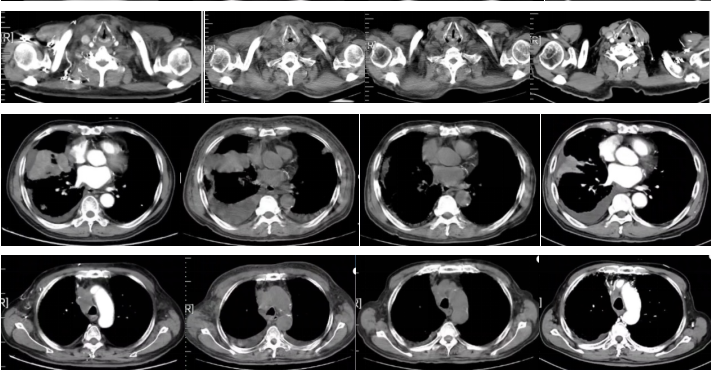

图5

该例患者为高龄、广泛期小细胞肺癌,初次就诊时合并双肺多发转移,且合并胸腔积液、心包积液等不良预后因素,预期生存短。患者一线采用经典的EP方案化疗,但疗效欠佳,PFS仅有3个月,且症状无明显缓解。

根据2022CSCO指南,广泛期小细胞肺癌患者≤6个月复发,二线治疗方案可选择拓扑替康或参加临床研究。但该患者对EC方案不敏感,且既往研究中二线采用拓扑替康疗效有限,且毒性较大。此外,该患者78岁,影像学可见合并双肺肺气肿、胸腔积液及心包积液,肺功能欠佳,体质较差,基于2022年ASTRUM-005研究公布的优异数据,综合考虑后,二线采用斯鲁利单抗联合白蛋白紫杉醇治疗。用药2周期后,患者肿瘤原发灶较前缩小,但转移灶却有不同程度增大,综合评效SD;用药4周期后肿瘤出现明显退缩,疗效达到PR。而肿瘤出现先增大后缩小这一反应模式是既往细胞毒药物治疗时代所不存在的,是肿瘤对免疫治疗的一种独特反应模式。在治疗过程中,患者未出现明显的免疫相关不良反应,耐受性良好。